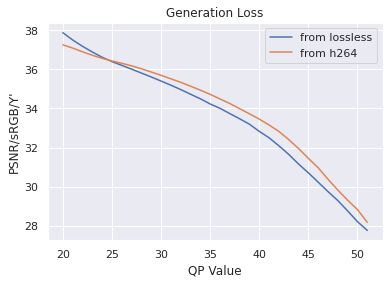

Since our dataset was compressed to be transferred from hospitals, we first investigated the impact of multiple stages of compression ("generation loss"). We used lossless video (24 seconds, 1.4GB) collected from an endoscope viewing dyed, non-human tissue. This gave the video the motion and texture characteristics of a colonoscopy. We then compared video quality between two compression schemes: compressing using H264 QP , where , and compressing to H264 QP20, then to H264 QP (when referring explicitly to this comparison, we will concisely refer to the latter as ’QP’). We then compared the average frame quality between these two schemes using two quality metrics (see ’Metrics’ section). The quality differences between these two compression schemes was minor in terms of PSNR-CbCr, which justifies our working with video data already compressed by H264 QP20.